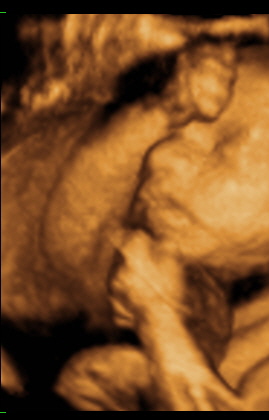

A mi kis álmodozónk